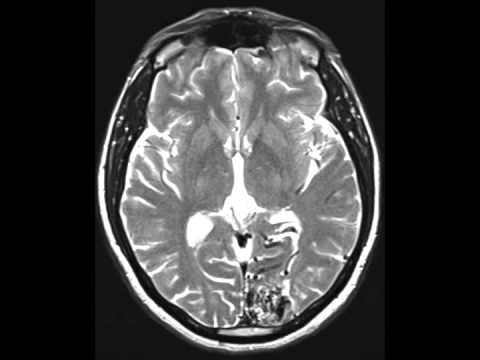

Hellow guys, Welcome to my website, and you are watching Microsurgical Resection of a Paramedian Parietal Arteriovenous Malformation. and this vIdeo is uploaded by Barrow Neurological Institute at 2021-01-19T14:26:10-08:00. We are pramote this video only for entertainment and educational perpose only. So, I hop you like our website.